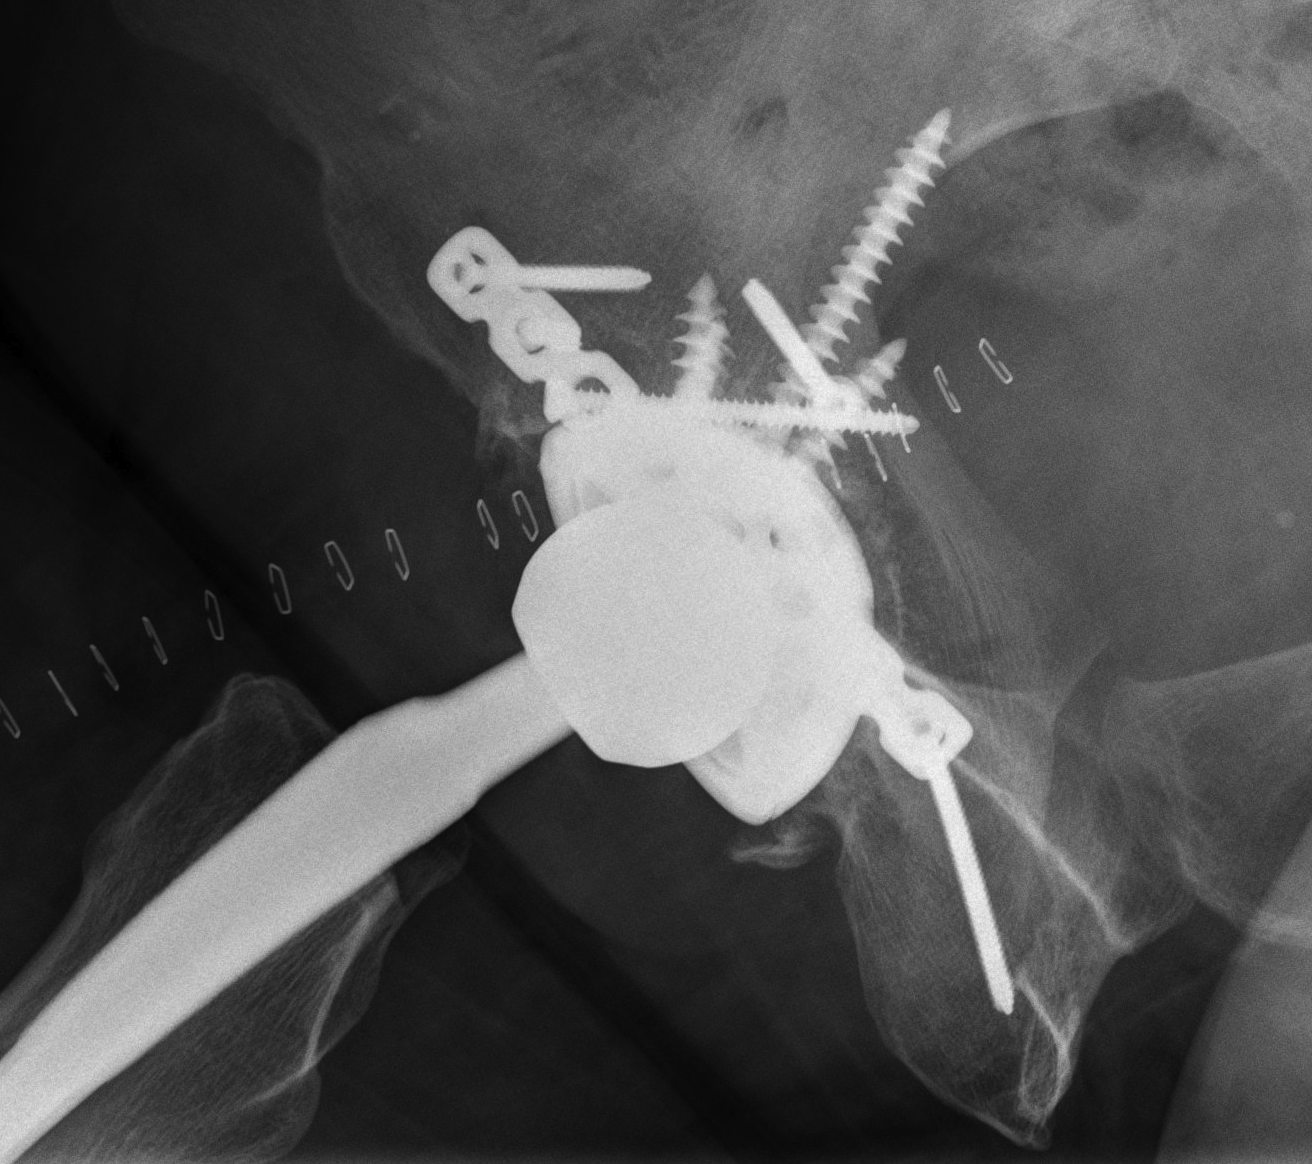

Intra-operative acetabular fracture

Postoperative acetabular fracture treated with double posterior plating